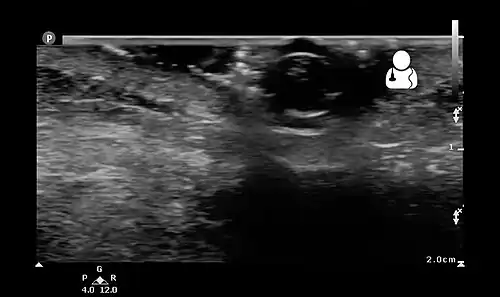

Ultrasound showing maggot infestation[24]